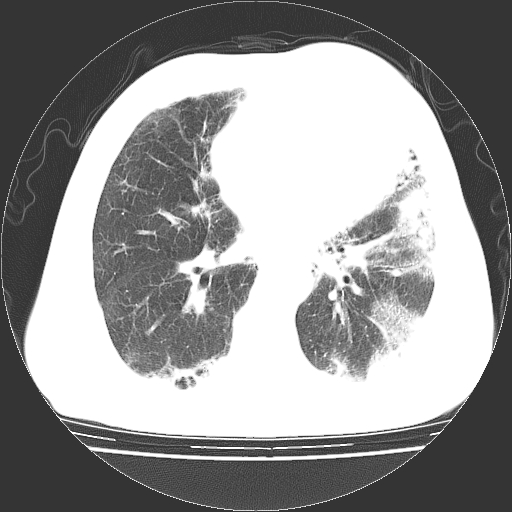

标题: CT25149:男,69岁,反复咳嗽、咳痰五年余,呼吸困难三天。 [打印本页]

男,69岁,反复咳嗽、咳痰五年余,呼吸困难三天。

慢支伴感染、肺气肿、肺心病

慢支伴感染、肺气肿、肺心病!支持!另:间质纤维化!

两肺间质性炎症并感染,左上叶肉芽肿

考虑慢性间质性肺炎并肺间质纤维化。

慢支伴感染、肺气肿、肺心病。双肺间质性改变(间质纤维化)。